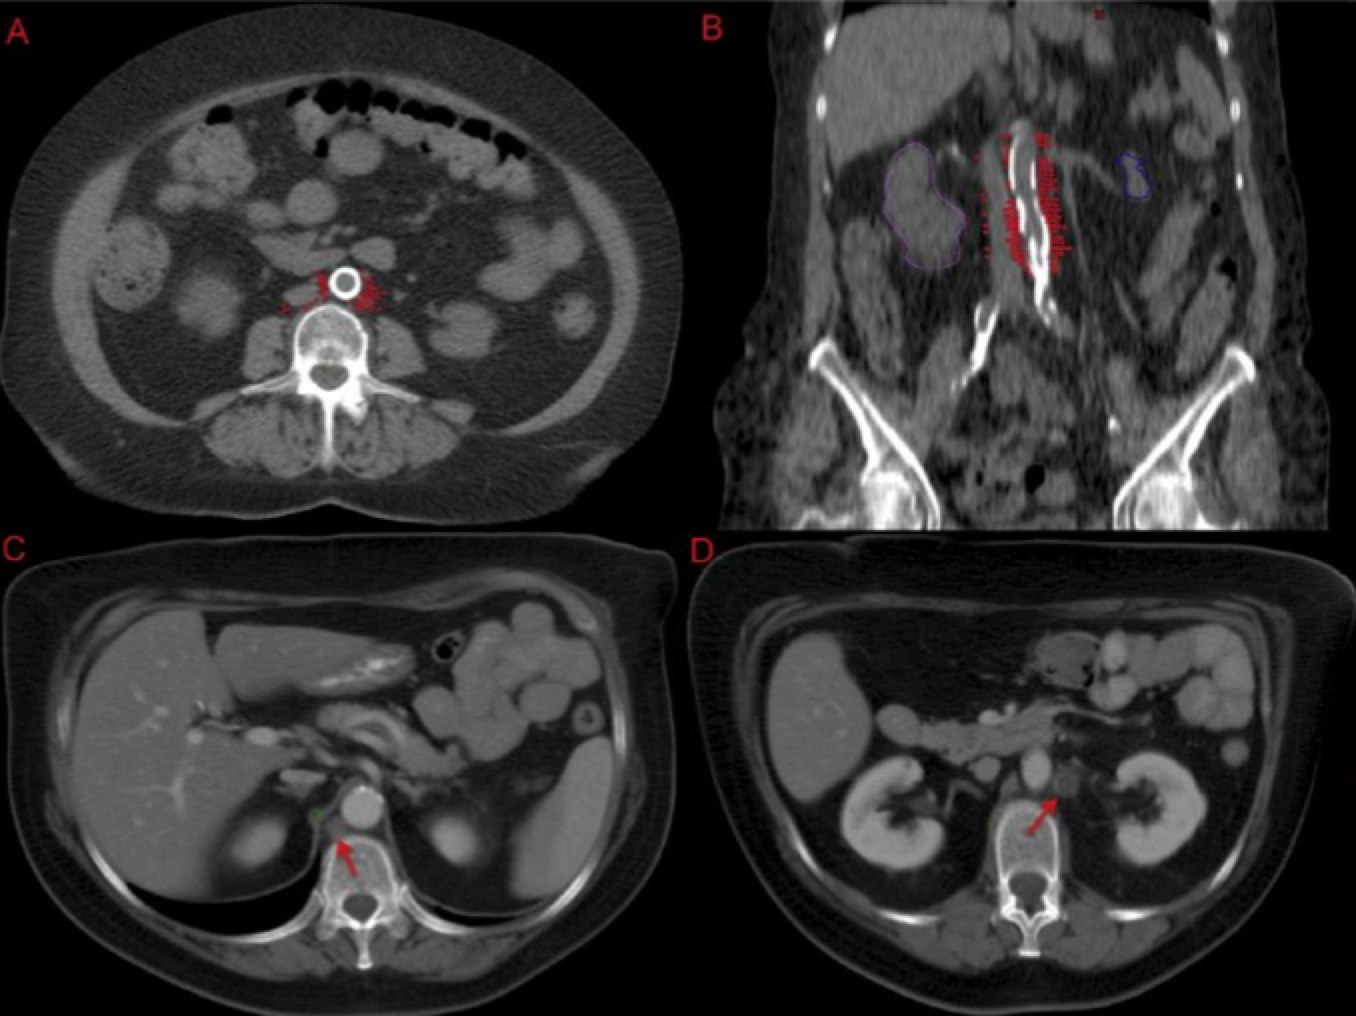

Most of the positive nodes are in the LEFT para-aortic region followed by the aorto-caval region. Few are located to the right of the IVC (inferior vena cava). Special attention should be paid to hte space on the LEFT LATERAL aspect of the aorta.